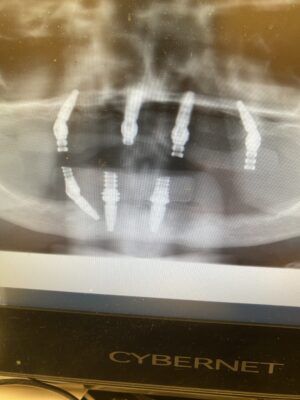

Drill protocol for D4+ bone. Only pilot drill? This is pt second upper attempt bc I couldnt get primary stability. I’ll try to engage nasal floor to help but eekk. Second attempt tmrw, these full arch cases kicking my butt lately.